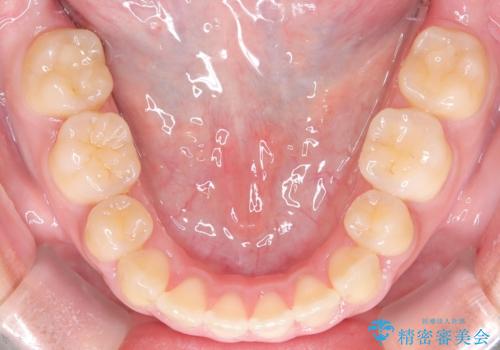

- 八重歯と口元が出ていることを主訴に来院されました。

レントゲンの検査において、前歯も外側に傾いてる結果であったため、上下左右の小臼歯を抜歯して配列を行いました。

歯の動きも良く短期間で治療を終えられたため患者さんにも大変満足していただきました。